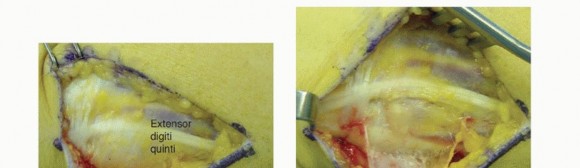

TECH FIG 2 • Open DRUJ/TFCC exposure and repair. A. Incision. B. Extensor retinaculum opened exposing fifth compartment. C. TFCC and DRUJ exposed. D. 3-0 nonabsorbable sutures placed through TFCC and ulna bone tunnels. E. Final construct demonstrating transfixation with 0.062-inch K-wires and TFCC repair.